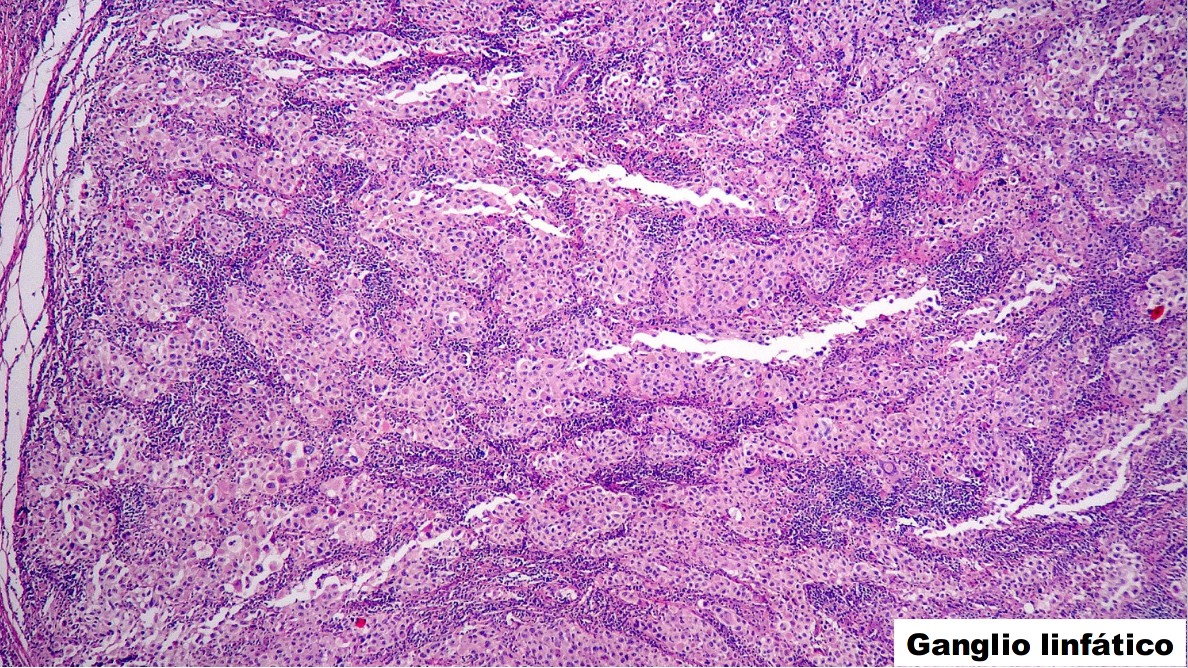

PA: Inició su padecimiento en el 2015 con adenopatía en región cervical derecha, sin otra sintomatología. Se realizó USG externo con reporte de adenopatía de 1.5 x 1.4 x 1.1 cm, y se realizó biopsia excisional.

PREGUNTA 1

Acorde a tu diagnóstico por H-E en ganglio linfático, ¿Qué batería de inmunohistoquímica pedirías con esa morfología?

A) CK7, CK20, P63, TTF-1, GCDFP-15

B) CKAE1-AE3, S100, CD45, VIMENTINA

C) CD45, CD3, CD20, ALK, CD68